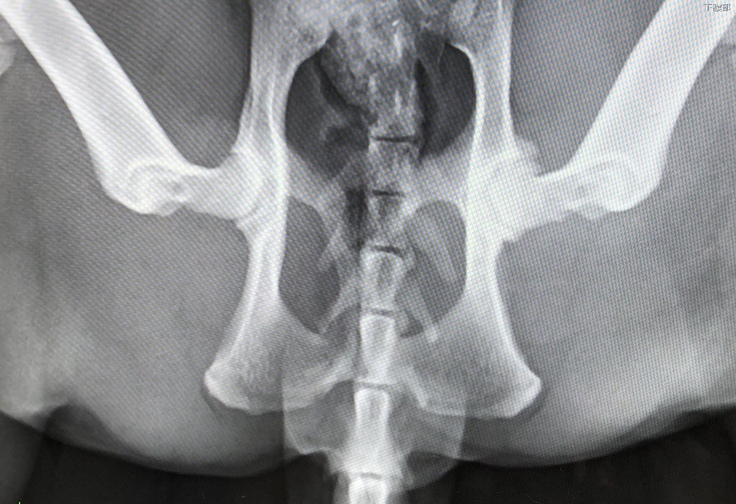

・レントゲン

脚のふらつきが改善しないため撮影。骨折、脱臼なし

※ただ、左股関節のはまりが浅いと言われました。

仰向けの画像なので向かって左側が左股関節です。

素人の私にはよくわからないのですが、モヤっと白いところが炎症してる所だそうです。

この時点では股関節の痛みから元気がないものと診断され、点滴処置と痛み止めと胃薬を処方してもらい様子見に。